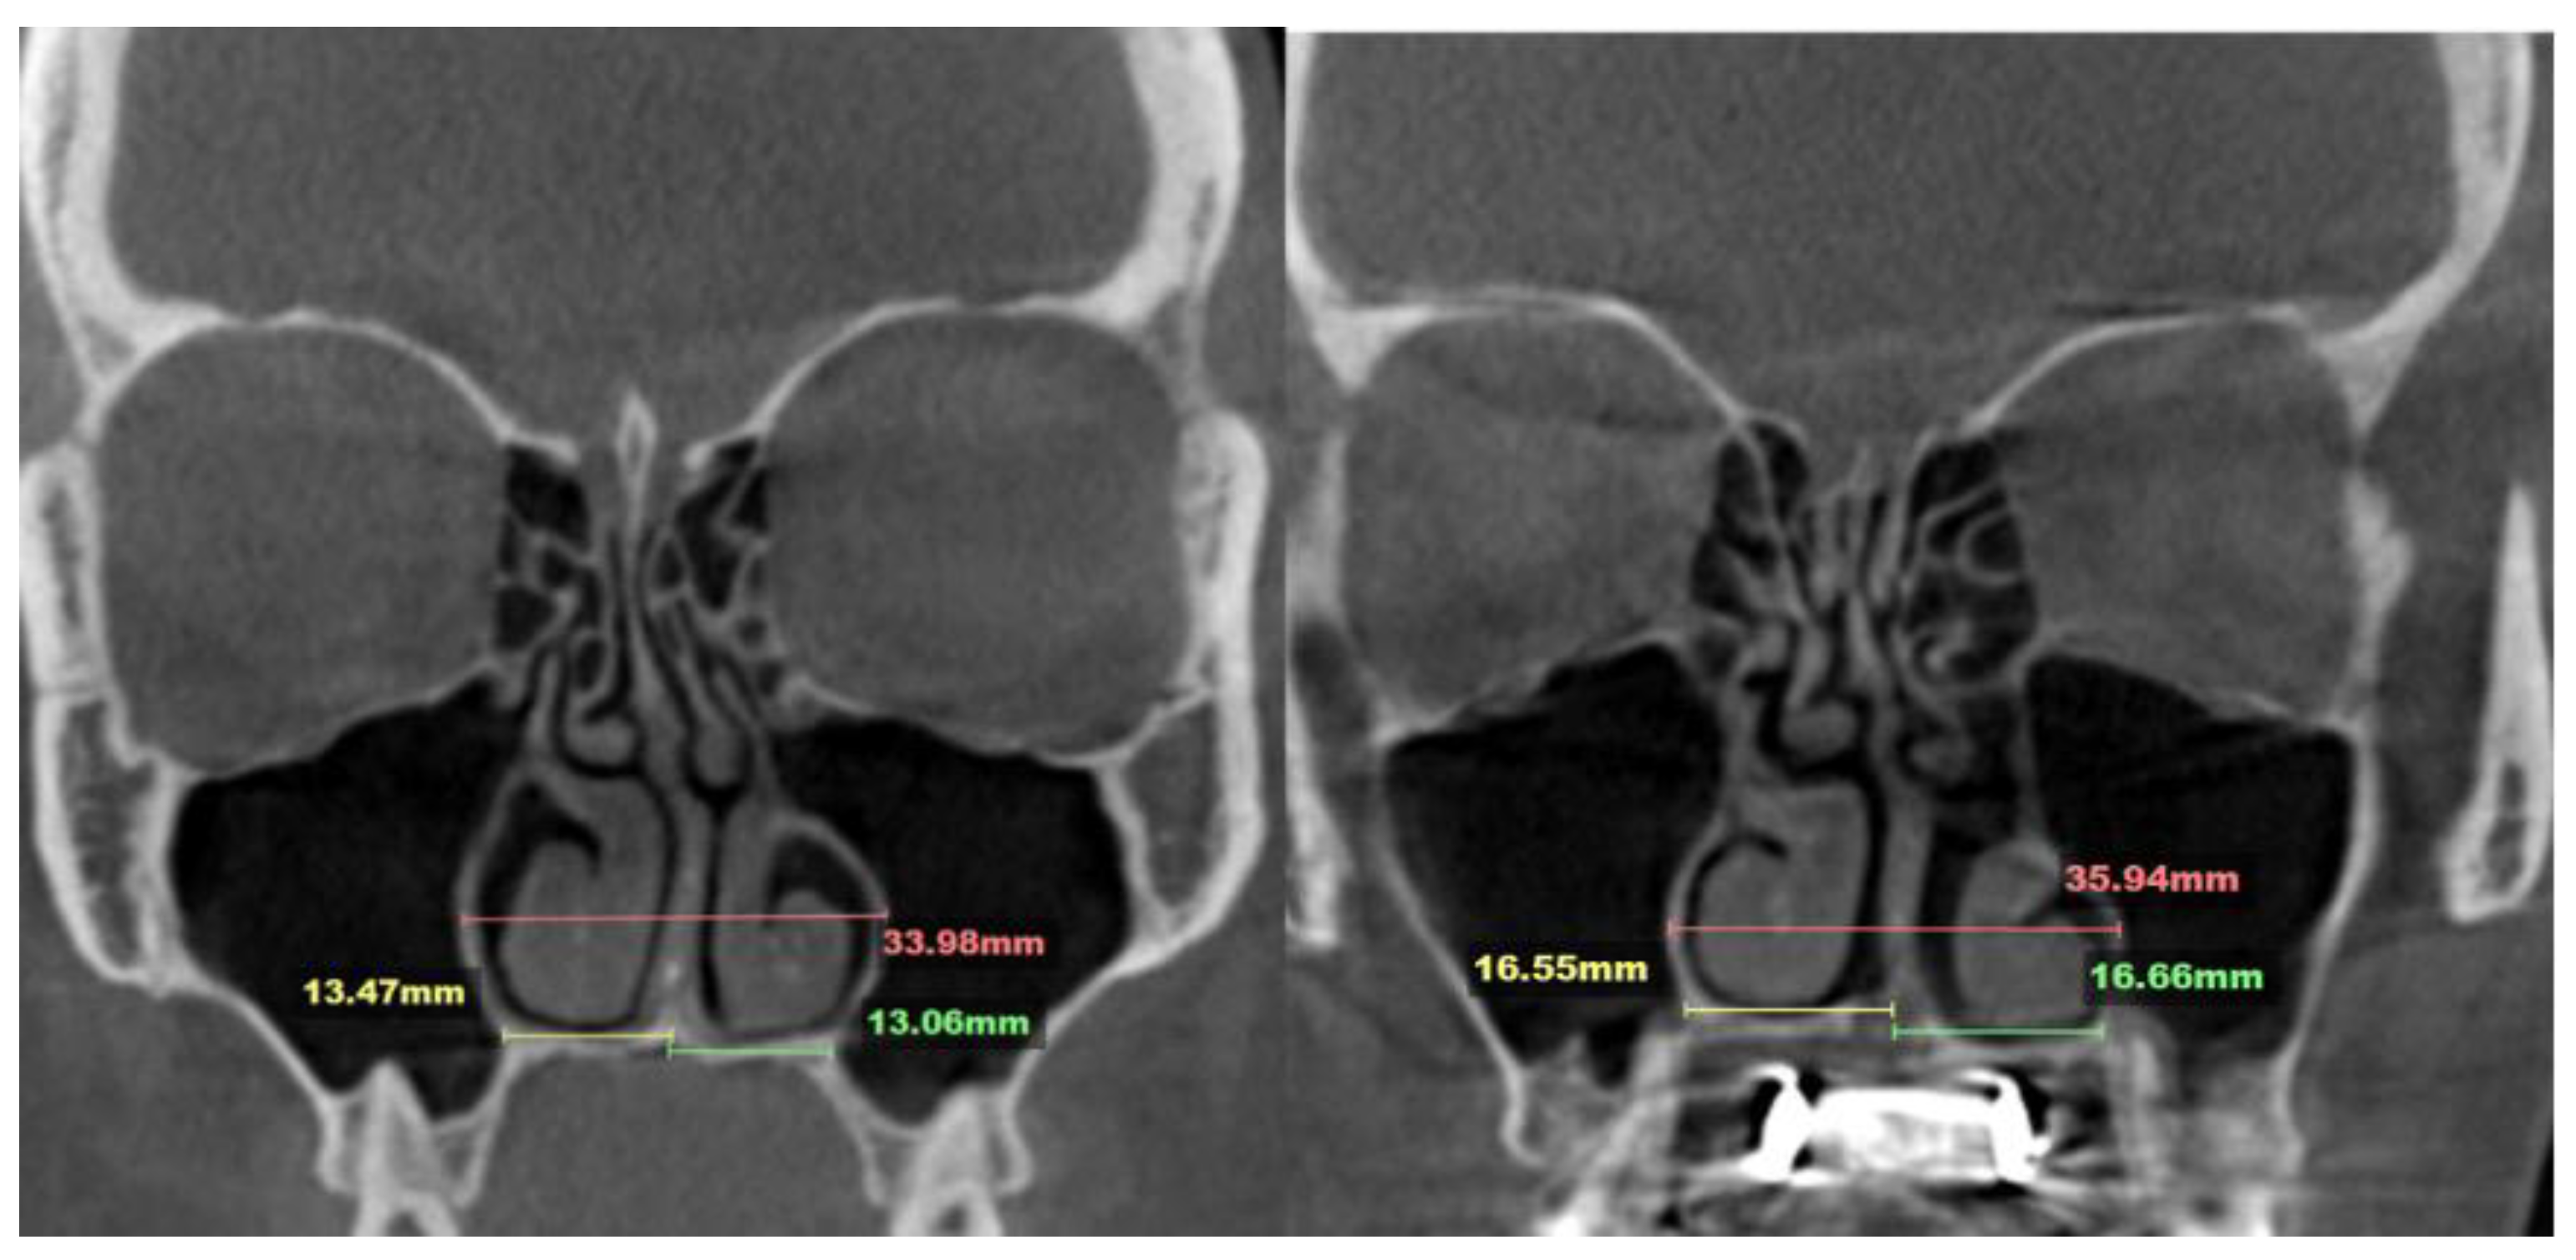

2.7. Case D: Midfacial Asymmetry Correction with Guided Expansion

- Asymmetric expansion with residual attachment of the nasal septum unilaterally to the maxillary crestal bone (Figure 5,6);

- Diagonal fractures of the palatine bone extending from the distal margin of the palatal process of the maxillary bone unilaterally, often associated with pain and tension;

- Asymmetric displacement of the nasal base floor with unilateral downward and outward movement (Figure 5,6)

- Downward inclination and displacement of the alveolar process on the ipsilateral side (Figure 5,6);

- Unilateral soft tissue shift, including nasal ala and corner of the mouth displacement toward the side of unattached separation.